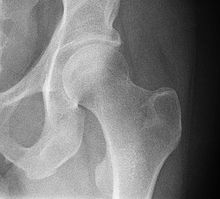

A hip fracture is a break that occurs in the upper part of the femur.[33] Symptoms may include pain around the hip particularly with movement and shortening of the leg.[33] The hip joint can be replaced by a prosthesis in a hip replacement operation due to fractures or illnesses such as osteoarthritis. Hip pain can have multiple sources and can also be associated with lower back pain.